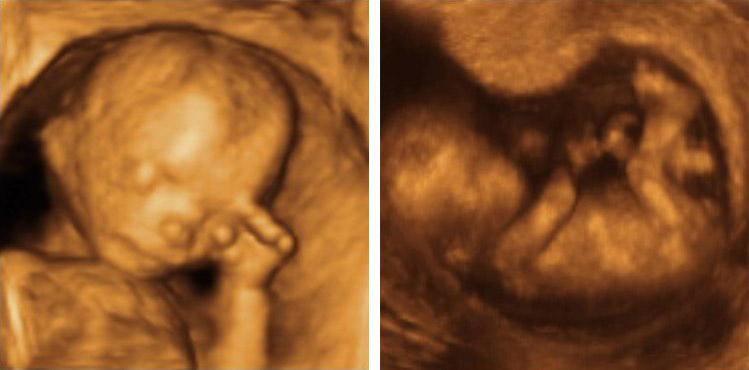

Чаще всего 4D-УЗИ применяется для осмотра плода внутри утробы. Преимущество такой процедуры — в том, что она дает возможность осмотреть тело ребенка сразу в трех проекциях. Это особенно важно для того, чтобы заранее получить представление о дефектах и аномалиях развития позвоночника, конечностей и черепа. С помощью процедуры можно диагностировать наличие пороков сердца, а также синдрома Дауна и прочих заболеваний, связанных с генетическими нарушениями.